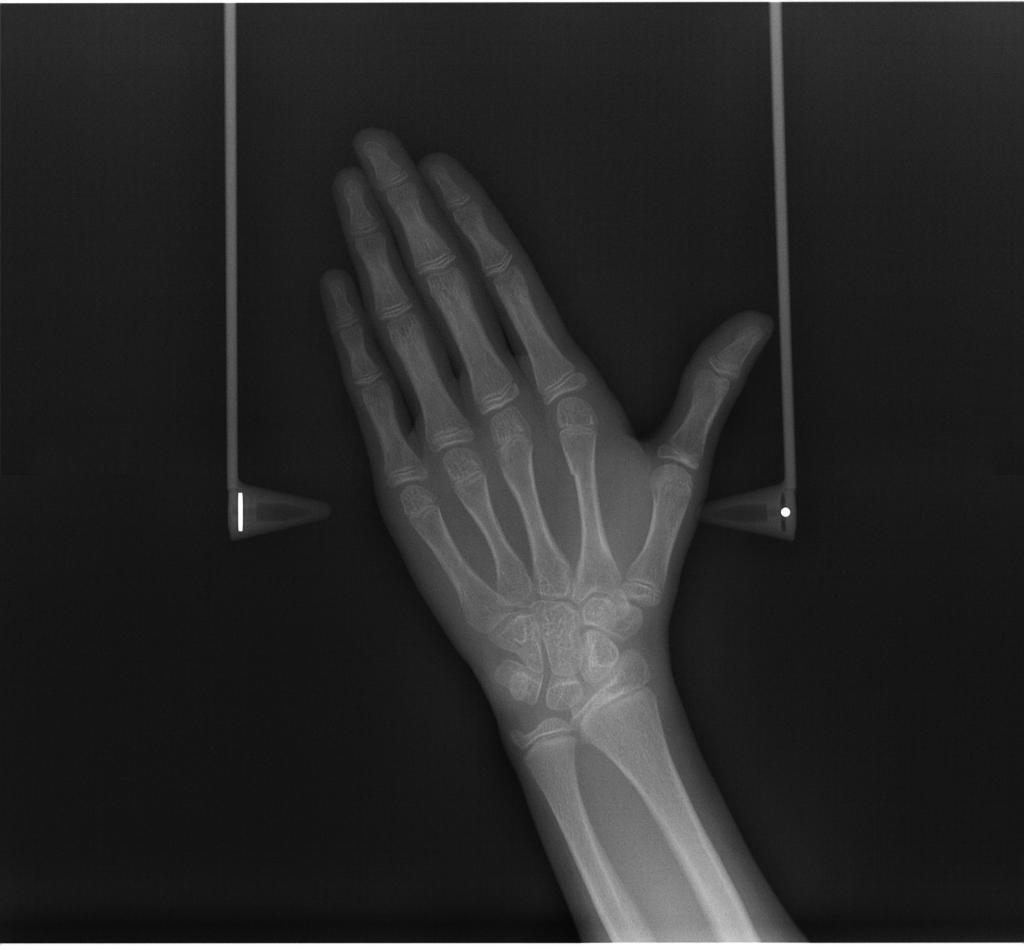

常规开展:数字化根尖片/横断牙合片、数字化口腔曲面体层片、头影测量侧位/正位片、手腕骨片、颅颌面CBCT、牙齿CBCT的检查以及涎腺造影、窦道 瘘管造影。

手腕骨片